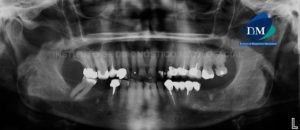

Paciente masculino de 17 años acude al Instituto de Diagnóstico Maxilofacial para evaluación de la pieza 2.1. A la evaluación de la radiografía panorámica se